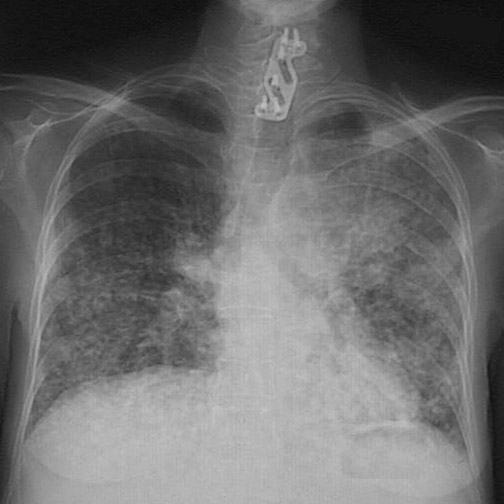

This chest radiograph demonstrates a more coarsely nodular pattern resulting from multiple metastases to the lung from a colonic adenocarcinoma. This is the same patient as the previous radiograph, but at a later point in the course. (The plate and screws in the cervical spine repaired a pathologic fracture from metastasis).